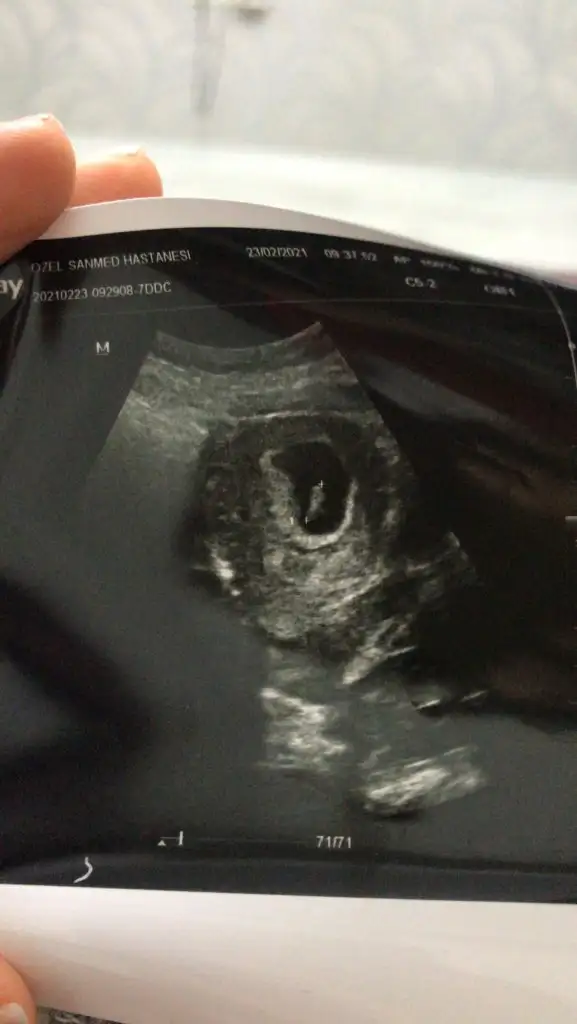

Selam cnm bana kız demiştin ama dr haftaya bakarız dedi belli olunca burdan yazıcam sana. Arkadaşımın ultrason reminede bakarmısın. karından bakılmış.

• IMG_20210227_130432.webp

21,6 KB · Görüntüleme: 71

• IMG_20210227_130403.webp

16,4 KB · Görüntüleme: 85